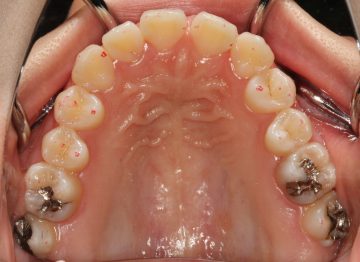

先天性欠如(生まれつき歯が足りない)の矯正症例

(19歳 女性 )

マウスピース型カスタムメイド矯正装置(インビザライン)単独によるスペースの確保、接着性ブリッジによるスペース閉鎖

治療前